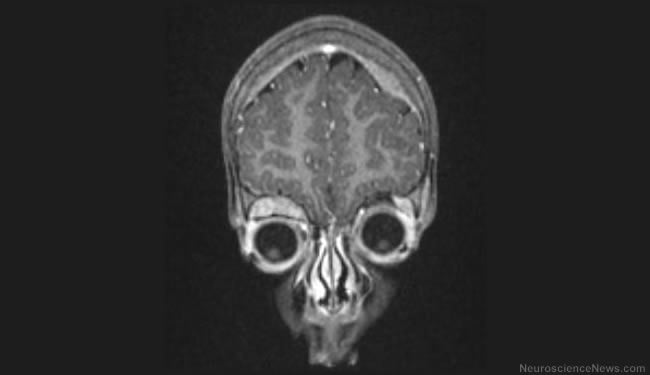

What Causes Brain Cancer? Understanding Glioblastoma

Understanding glioblastoma at the genetic, molecular level Glioblastoma is the most common and most lethal form of brain tumor in...